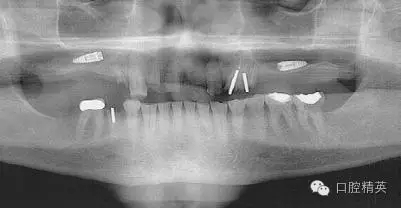

我們通過文獻(xiàn)和網(wǎng)站檢索獲得了一些關(guān)于種植體失敗的研究和綜述文章。一個(gè)和僅使用兩維放射診斷(根尖片或曲斷片)有關(guān)的常見失敗是上頜竇穿孔。(圖1a-c)通常牙醫(yī)由于錯(cuò)誤的估計(jì)了上頜竇底骨量高度而造成幾個(gè)毫米的上頜竇底穿孔。一些病例可能沒有癥狀,象圖中所示的這個(gè)病例,患者需要嚴(yán)格的監(jiān)控、復(fù)查。有些病例則出現(xiàn)并發(fā)癥,種植體不得不取出。

另一個(gè)和醫(yī)生僅用兩維放射線檢查造成的特殊并發(fā)癥是種植體進(jìn)入上頜竇。(圖2a-c)可能成為上頜竇異物的有牙齒,牙根,印模材料,牙科器械,近年來又增加了一個(gè)—種植體??上攵瑥纳项M竇中取出異物對(duì)患者來講是創(chuàng)傷很大的。

其他研究也報(bào)道過,對(duì)于這種病例,唯一的選擇是用根管顯微鏡或Caldwell Luc技術(shù)從上頜竇中取出種植體。有些文章報(bào)道了如何處理進(jìn)入上頜竇的種植體,但很少?gòu)念A(yù)防的角度來談這個(gè)問題,其實(shí)很簡(jiǎn)單,術(shù)前應(yīng)該應(yīng)用CBCT成像檢查。